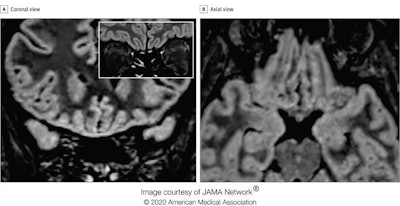

Follow-up MRI in the same patient 28 days from symptom onset. Coronal (A) and axial (B) reformatted 3D FLAIR images show complete resolution of the previously seen signal alteration within the cortex of the right gyrus rectus. In the inset, a coronal 2D FLAIR image shows a slight reduction of the hyperintensity and the thickness of the olfactory bulbs, suggesting a postinfection olfactory loss.The authors found no brain abnormalities in two other patients with COVID-19 who presented with anosmia and who underwent brain MRI 12 and 25 days from symptom onset.